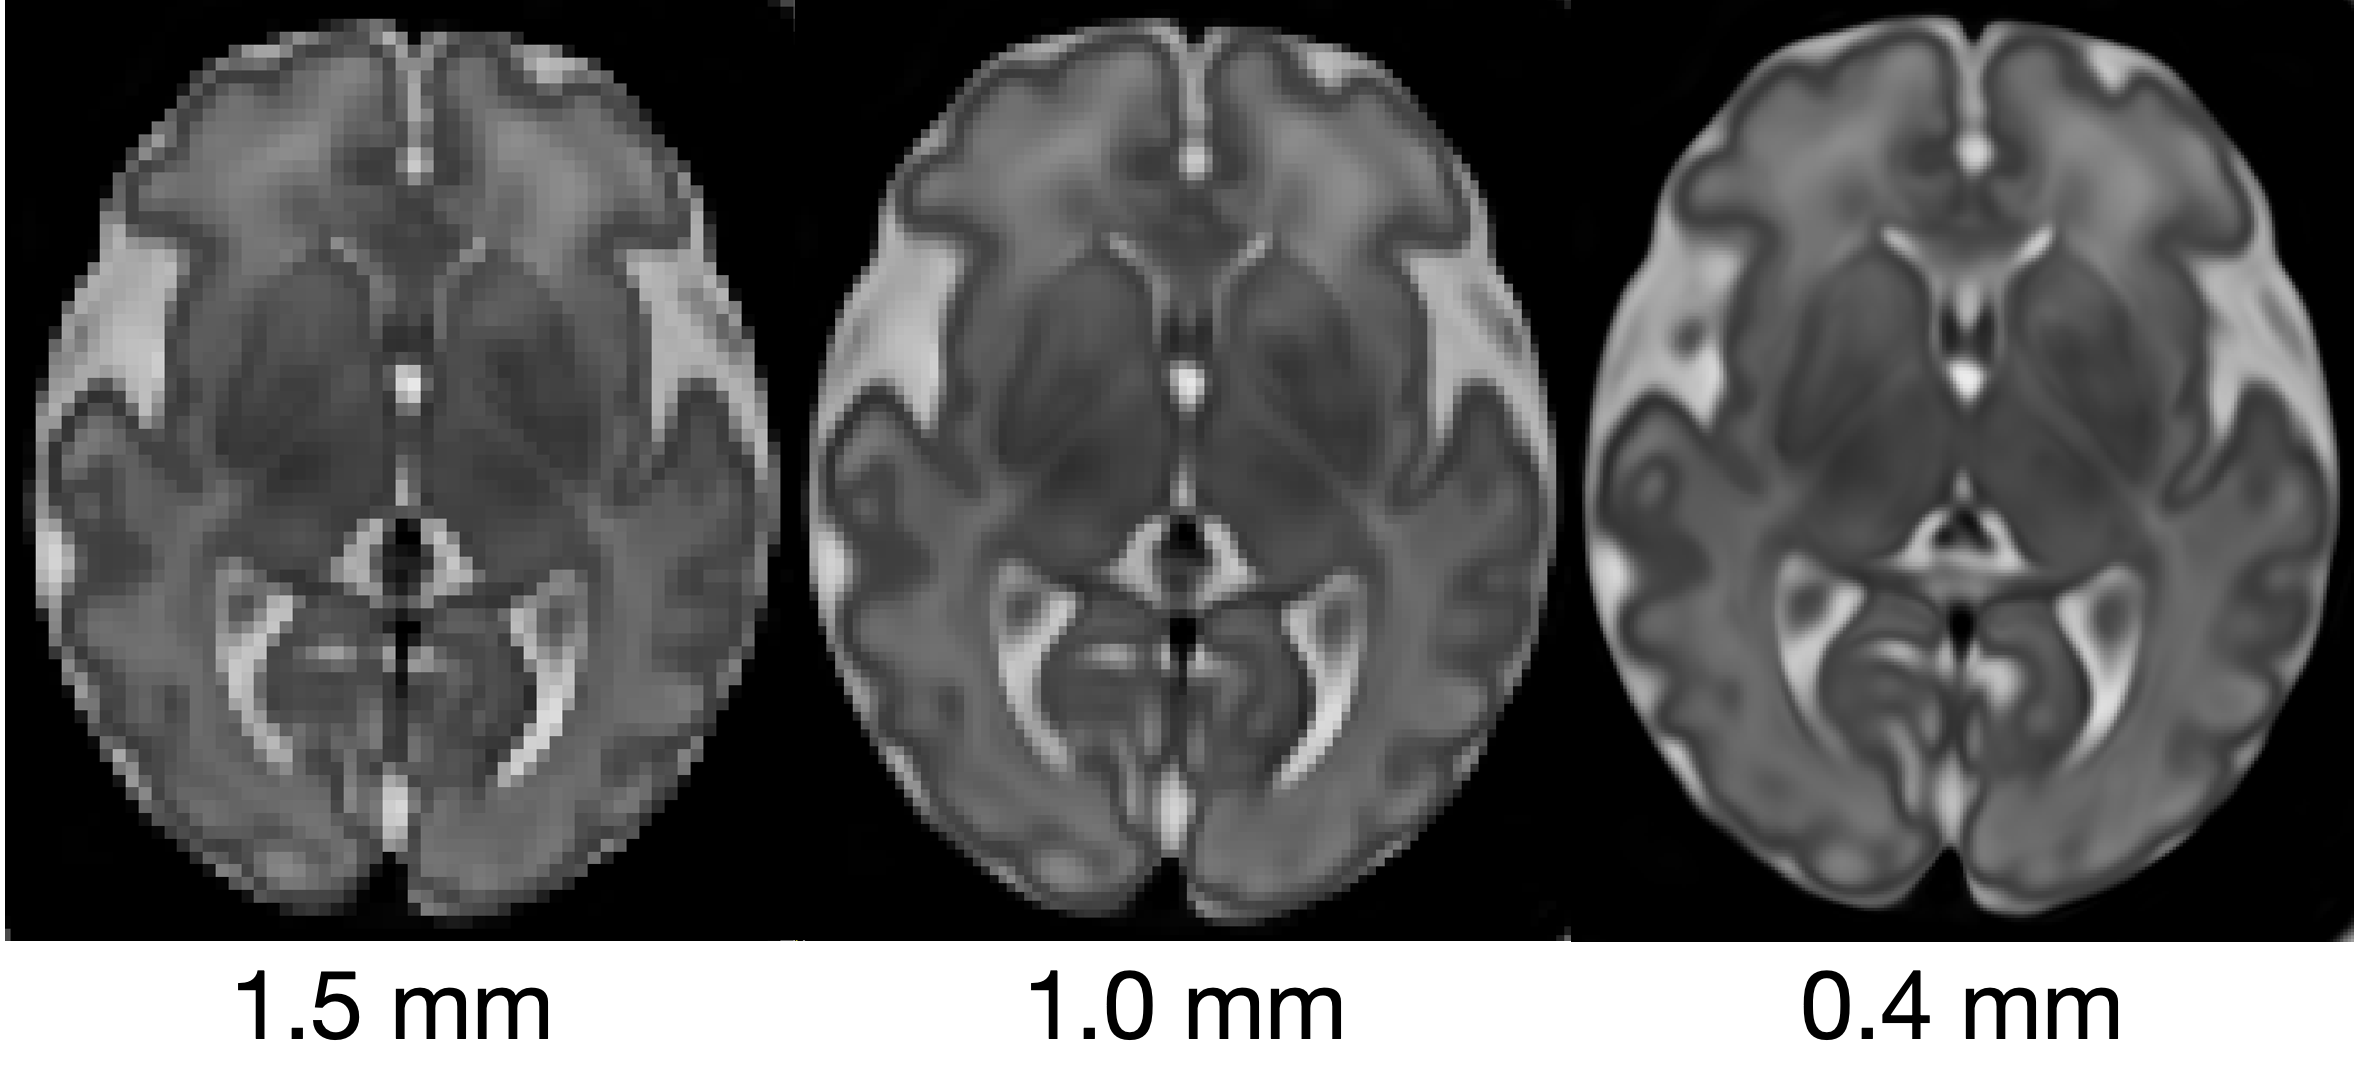

Refer to caption

Figure 6: CINA is resolution agnostics allowing us to generate an atlas of arbitrary spatial resolution. Left to right shows an atlas for a specific time point of increasing spatial resolutions of 1.5mm, 1.0mm, and 0.4mm isotropic voxel spacing.